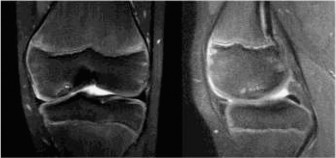

The patient then obtains the following radiograph (Fig. 10–22) which confirms the diagnosis of an OCD lesion of the medial femoral condyle. An MRI is then ordered to examine the lesion further. A T2 image is shown in Figure 10–23.

Figure 10–22

Figure 10–23

The correct answer is (C). The patient has an OCD lesion of the posterolateral aspect of the medial femoral condyle which is the most common location for these lesions. Pediatric patients have a much better prognosis for OCD lesions as open distal femoral physes are the best predictor of a successful outcome with nonoperative management. Lesions which have synovial fluid behind the lesion on MRI are potentially unstable and require much more aggressive surgical management to prevent detachment and separation. As this patient is young, has open distal femoral physes, and has no instability on MRI, a trial of conservative treatment is appropriate. Arthroscopic drilling (either antegrade or retrograde) can be performed for stable lesions which have not responded to a trial of conservative management (Fig. 10–24). Open reduction and internal fixation should be reserved for unstable lesions.